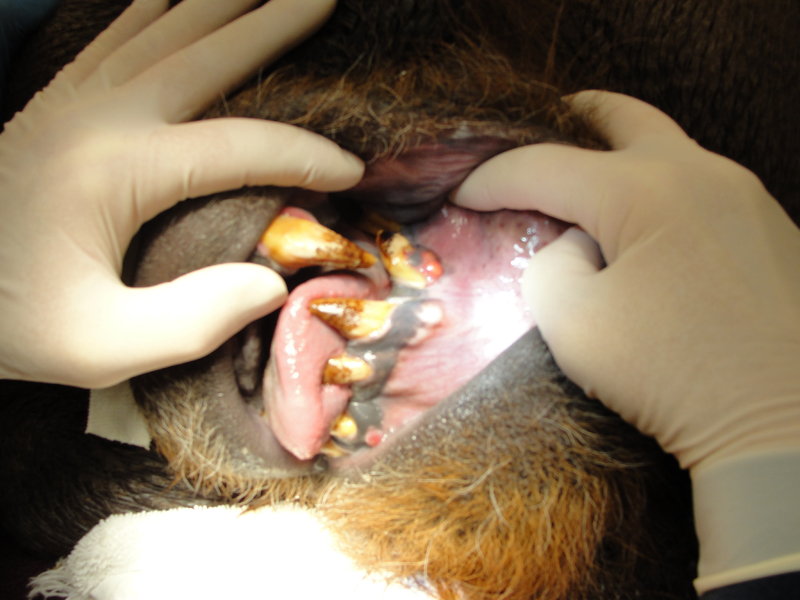

Most or our orangutans however, have had chronic, serious periodontal disease. All of our males have eventually lost all their teeth due to periodontal disease. That has not been the case with the females. We are not the only zoo that has had the chronic periodontal problems with orangutans. See Dr. Norm Stollers' paper: In the typical orangutan case that I have dealt with, there is not much accumulation of plaque or calculus. However, deep periodontal pocketing and bone loss progresses until the teeth become very mobile. I have not observed much bleeding in the most severe of these cases. We discussed preventive strategies and even tried chlorhexidine gluconate rinses to subdue the disease process. However, the orangs did not accept the products, probably due to the taste.